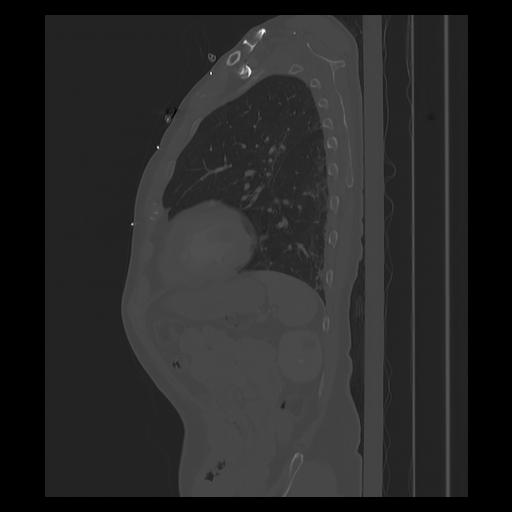

33 PULMON,CE,Sagittal,3.000,PULMON,Sagittal,